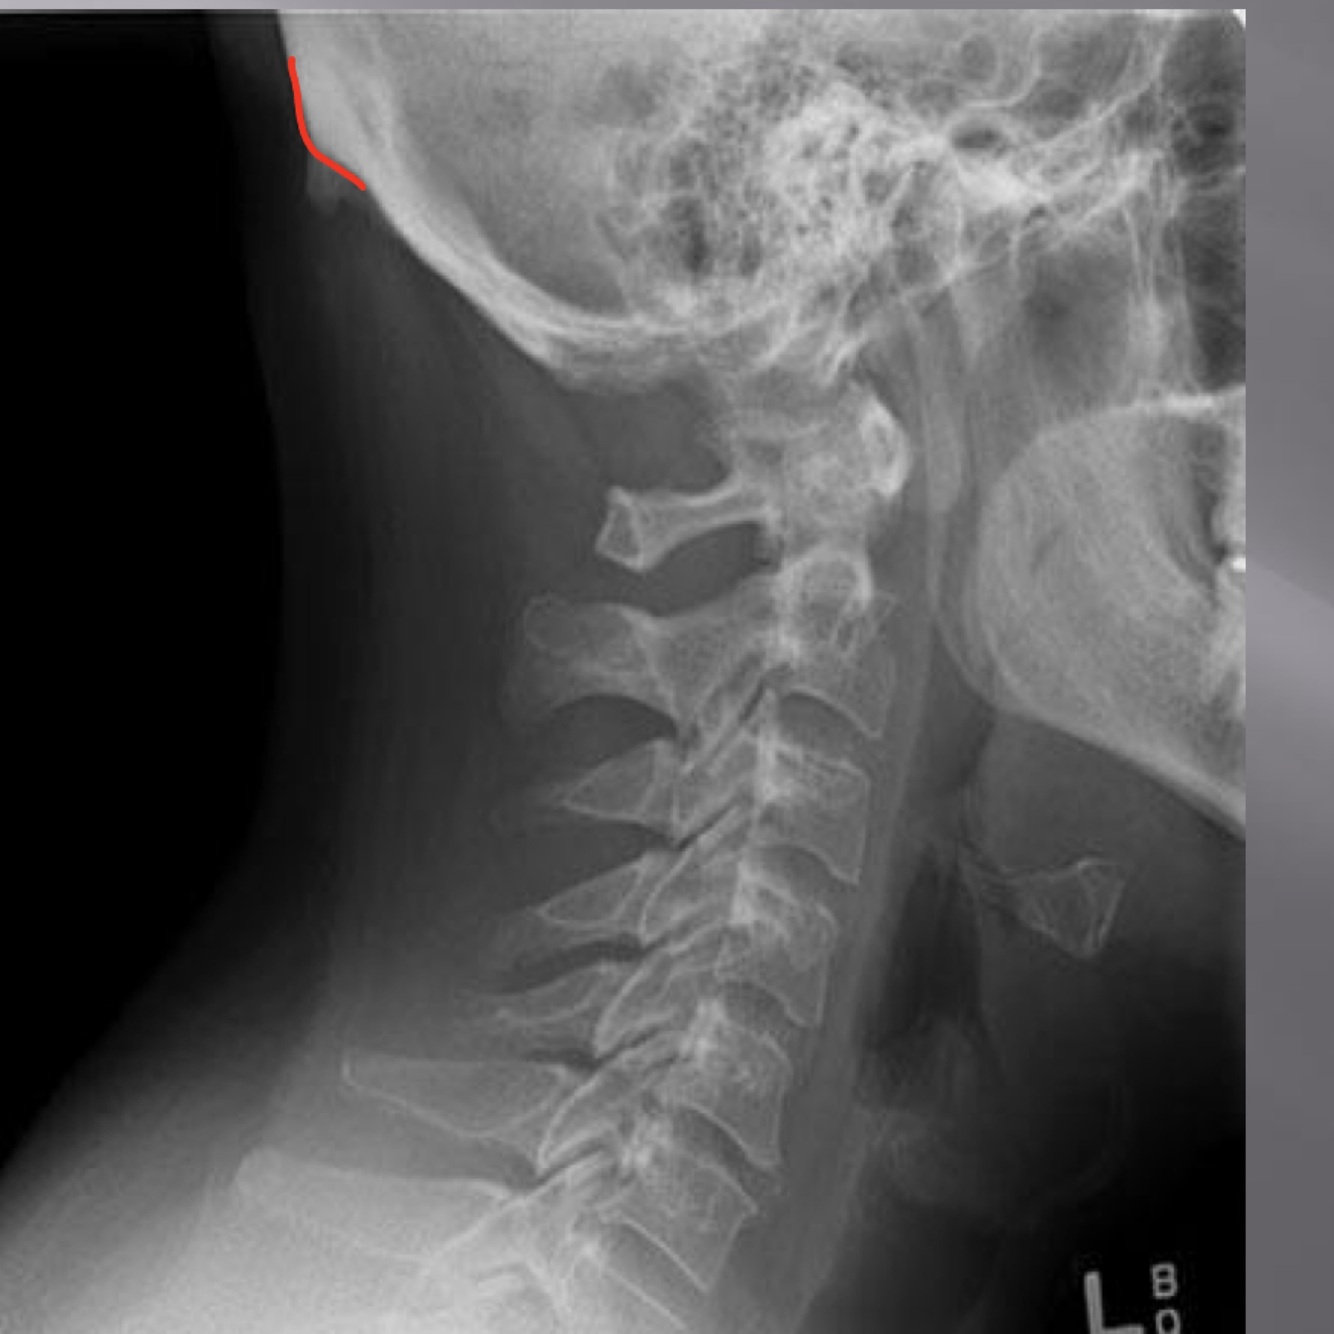

LATERAL CERVICAL LANDMARKS lateral cervical view

external acoustic meatus

Lateral cervical view

mastoid process (air cells)

posterior tubercle of c1

angle of mandible

Q

EOP

spinous process C2-C7

sella turcica

dens

posterior arch of C1

lamina c2-c7

vertebral body c2-c7

rami of mandible

body of mandible

anterior tubercle c1

zygapophyseal joints

petrous portion

occipital condyle

Lateral cervical

superior endplate tips

inferior endplate tips

disc spaces

atlanto-dental interspace

hyoid bone